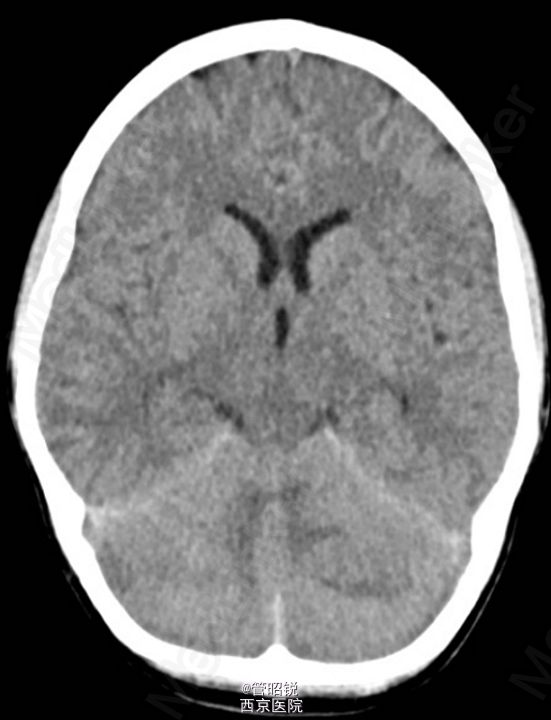

患者,男,29岁,头痛、颈痛2周 入院时CT正常,24小时后 T2WI (B) 和 T2W-FLAIR (C)显示高信号增强,脑水肿,沟回消失。CE-T1WI (D)显示脑膜线样增强。随后12小时的非增强CT显示小脑水肿压迫脑干,由于阻塞性脑积水使颞角膨大,需要紧急行颅后窝颅骨切除减压术。(影像资料比较典型。和大家分享下 AJNR-case of the week)

诊断:急性小脑炎 治疗上应早期应用激素治疗,水肿严重时应手术行颅骨减压。

急性小脑炎是以小脑功能损害为主的炎性综合症。发病前期一般有感染病史,多见于儿童。临床表现多样,主要有躯干和肢体的共济失调,发热,眼球运动异常,言语不清,头痛,恶心、呕吐和意识水平的下降。临床诊断主要依据其典型的影像学检查,临床表现和脑脊液检查结果。